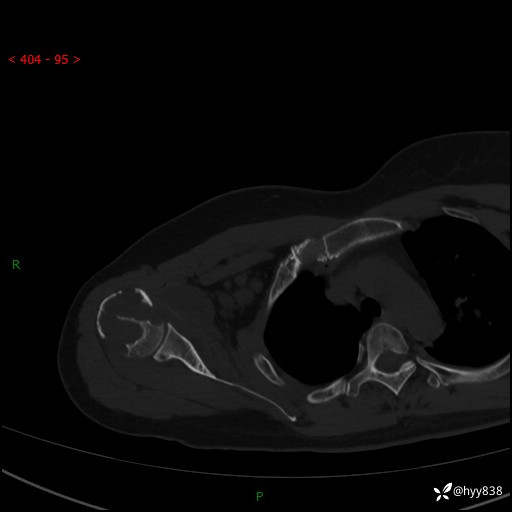

中年女性,发现右肩关节占位2天。有特征、有细节---结果公布~

年龄:47岁

主诉:发现右肩关节占位2天

现病史:患者3年前摔伤致右肩部疼痛,未行特殊处理,后右肩活动时轻度疼痛,患者未引起重视。1月前上述症状加重,于当地县人民医院就诊,2023-07-10右肩关节MR:右肱骨头、肩胛骨及周围软组织异常信号。现患者右肩可触及质硬包块,活动时疼痛,无头晕头痛、恶心呕吐、腹痛腹胀等,为求进一步治疗,来我科就诊,门诊以“右股骨占位性病变”收入我科。 起病以来,患者精神、饮食、睡眠可,大小便正常,体力、体重未见明显变化。

右肩关节CT平扫